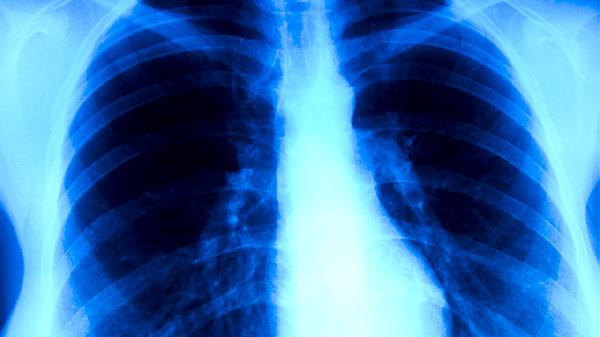

耐药性肺结核的危害较大,可能增加治疗难度、延长病程并提高传播风险。耐药性肺结核通常由不规范用药、治疗中断或感染耐药菌株引起,需通过药敏试验确诊并制定个体化方案。

建议确诊患者严格隔离治疗,完成全程用药并定期复查痰菌和影像学。接触者应进行结核菌素试验筛查,高风险人群可预防性使用左氧氟沙星片。日常保持室内通风,佩戴口罩减少飞沫传播,保证高蛋白饮食和充足睡眠增强免疫力。出现持续咳嗽、低热、盗汗等症状时须及时就医进行痰培养和药敏检测。